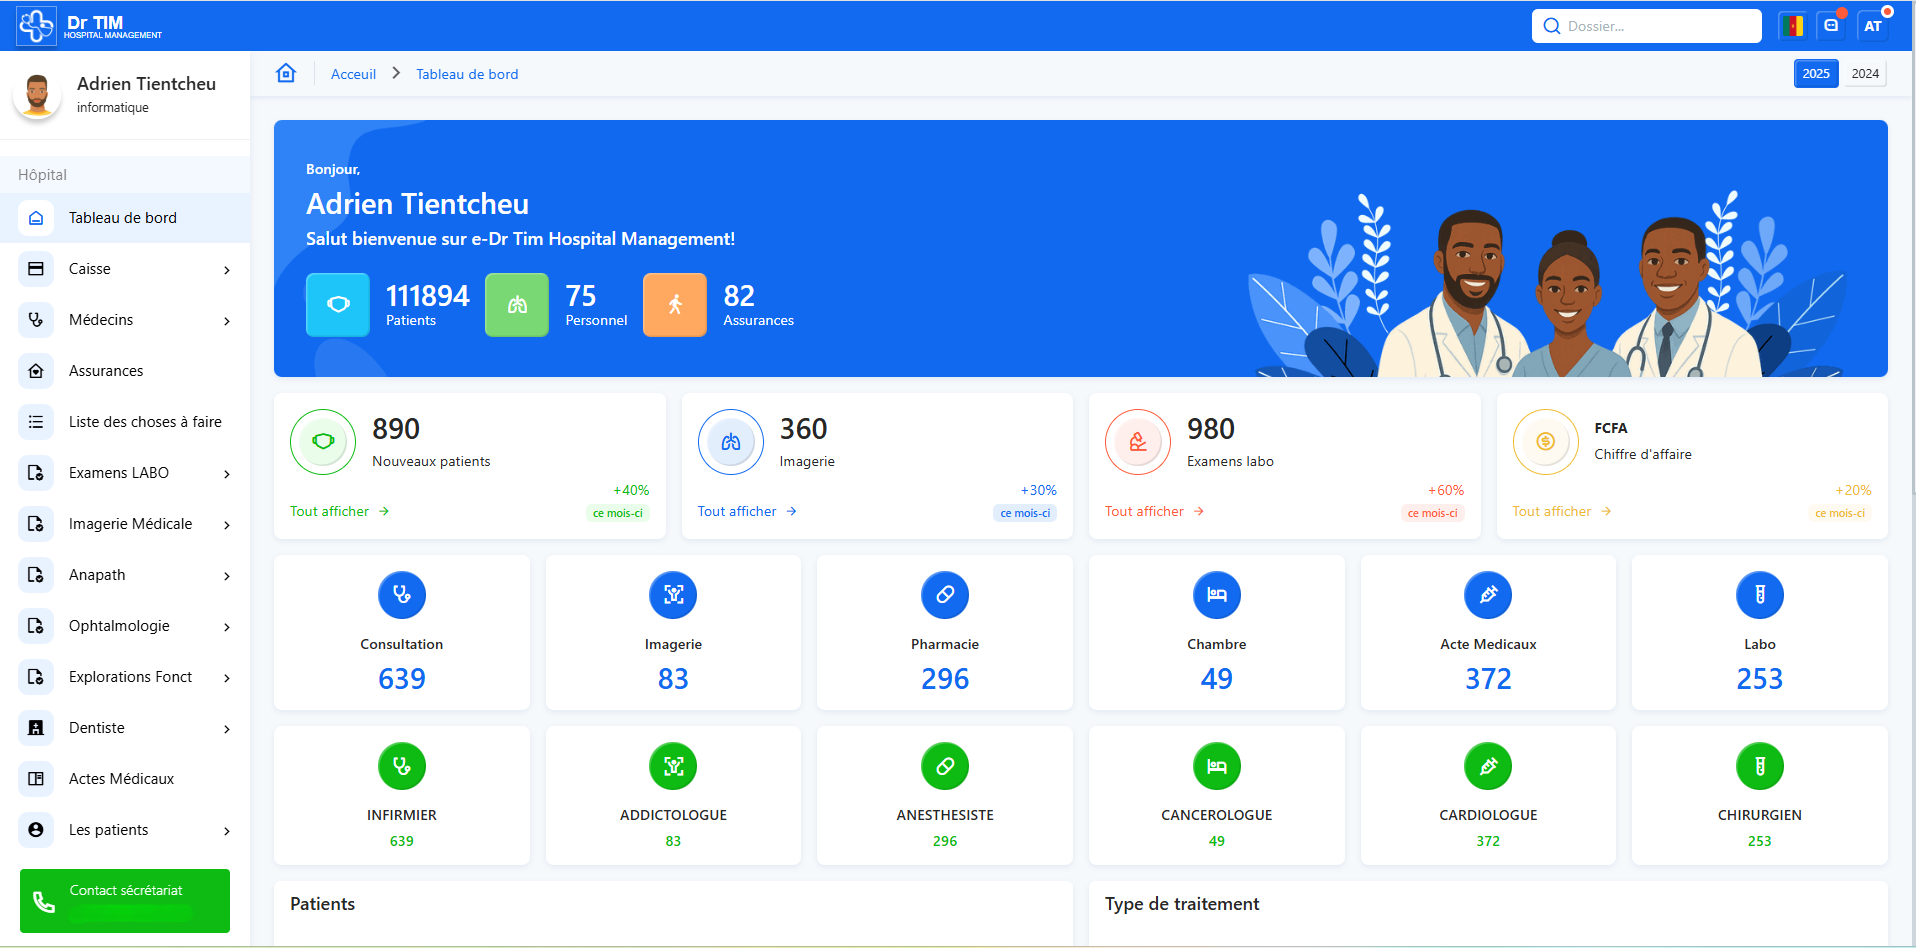

L'Écosystème

e-Dr Tim

La révolution numérique de la santé, à portée de main. Découvrez nos applications innovantes conçues pour les patients et les professionnels de santé.

Pourquoi Choisir e-Dr TIM?

e-Dr TIM révolutionne votre expérience de santé grâce à une plateforme intelligente, sécurisée et étonnamment simple à utiliser. Prise de rendez-vous, suivi médical, gestion des dossiers, échanges avec les professionnels de santé : tout est centralisé pour vous faire gagner un temps précieux et vous offrir un accompagnement fluide au quotidien. Reprenez le contrôle de votre santé en toute sérénité, avec un outil pensé pour votre confort et votre sécurité.

Mise à disposition gratuite d'équipements

Avec e-Dr Tim Hospital Management, profitez gratuitement d’équipements adaptés pour exploiter pleinement les modules essentiels de votre clinique. Nous vous accompagnons avec des solutions sur mesure, renforcées par la mise à disposition d’outils répondant précisément à vos priorités cliniques.

Un Controle Total Sur Vos Recettes

Avec e-Dr Tim Hospital Management, maîtrisez entièrement vos recettes : contrôle des irrégularités liées aux bons d’assurance, facturation transparente et fiable. Les fraudes disparaissent, vos revenus sont sécurisés. Concentrez-vous sur vos patients, e-Dr Tim veille sur vos finances.

Numérisation Du Dossier Médical

Fini le papier et les documents égarés : tous vos dossiers patients sont désormais centralisés, parfaitement sécurisés et accessibles à tout moment. Vous gagnez en fiabilité, en rapidité et en tranquillité d’esprit.

Nos modules

Voici les modules clés qui font d’e-Dr Tim une solution complète, flexible et parfaitement adaptée aux exigences de votre activité.

Hospital Management

La Technologie au Service du Soin : Gérer Intelligement, Soigner Mieux

Une plateforme de santé digitale complète, pensée pour optimiser l’accès aux soins, moderniser la gestion hospitalière et renforcer la relation entre patients et médecins grâce à la digitalisation et à la mobilité.